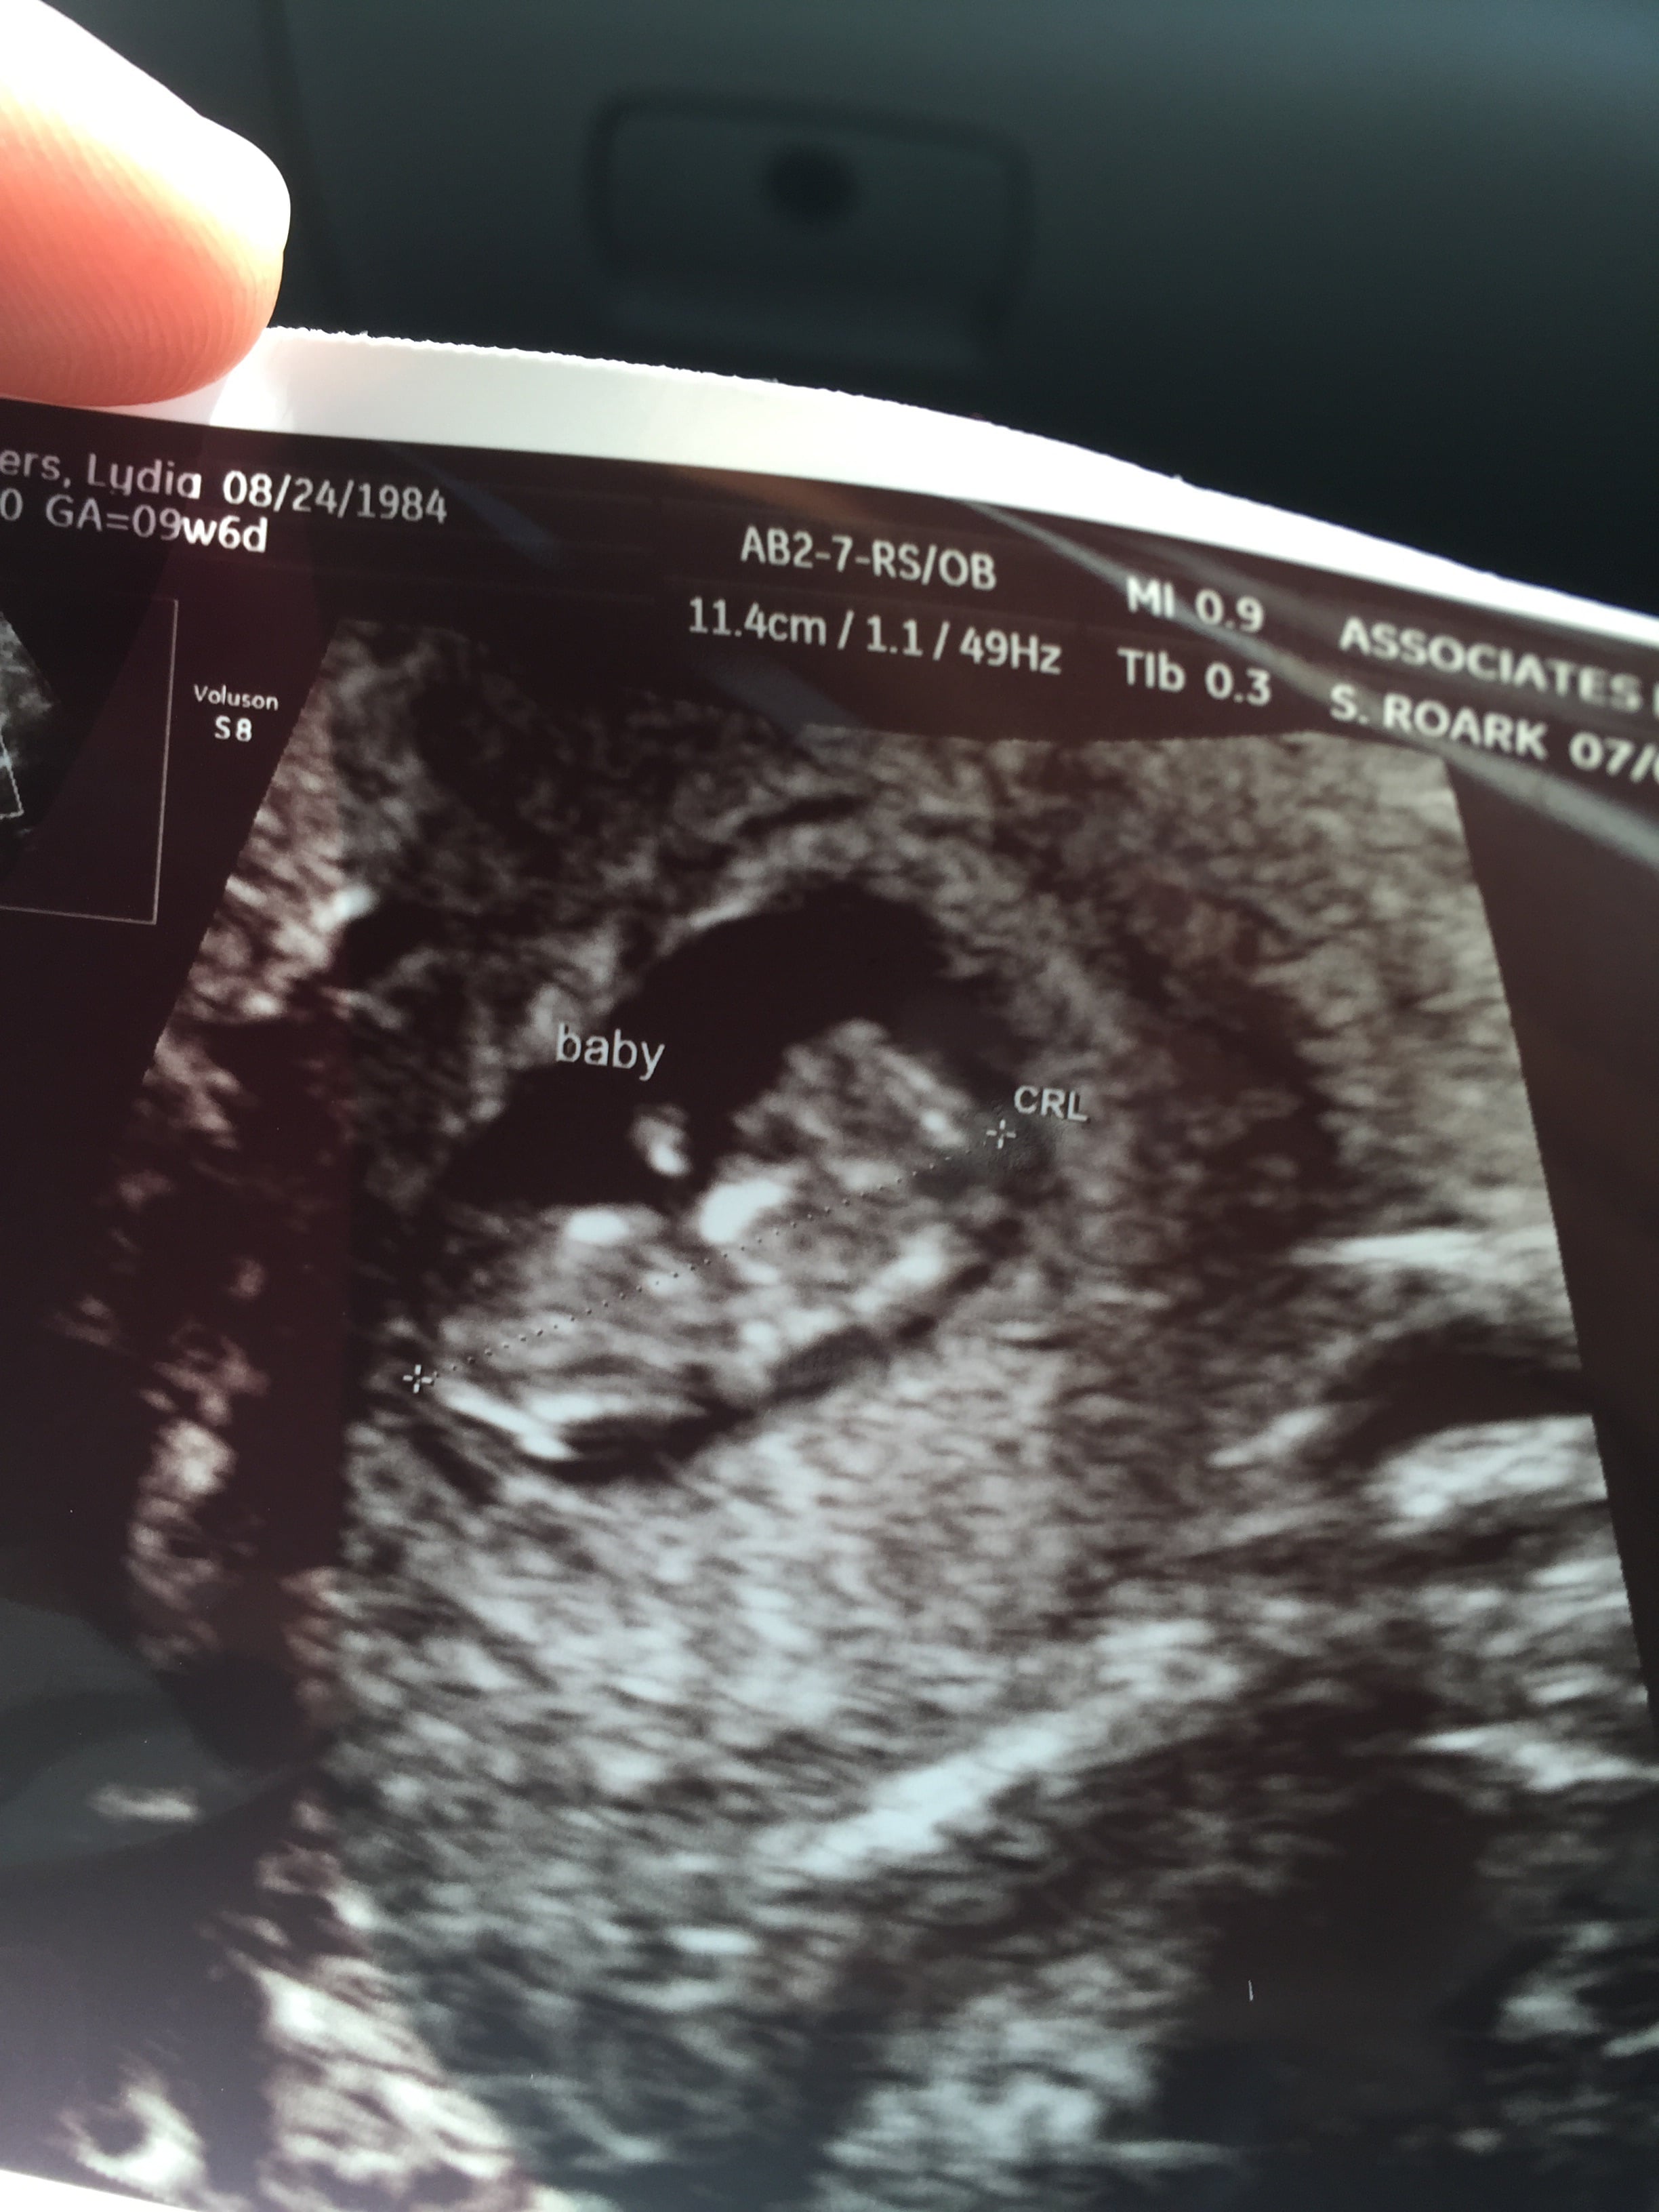

• So glad I get to finally post on this thread! First US today. I was really worries because my progesterone was low, but baby looks good :) heartbeat was 143. Not as far along as we originally thought, but not far behind. Right at 7 weeks. Due 2/23 :)